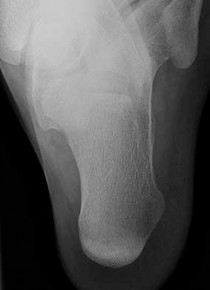

Figures 1a through 1c

Tarsal coalitions occur when primitive mesenchymal cells fail to differentiate and form the

normal articular separations between the tarsal bones of the hindfoot. Overall incidence is difficult to determine because many affected people are minimally symptomatic or asymptomatic. Symptomatic tarsal coalitions typically present in adolescents as a painful flatfoot; however, there are a number of possible presentations, and occasionally symptoms do not appear until adulthood. Most tarsal coalitions are between the calcaneus and the navicular (CN) and the talus and the calcaneus (TC). Although most TC coalitions are across the middle facet, posterior facet coalitions do occur. Plain radiographic evaluation of suspected tarsal coalition is the mainstay for diagnosis. However, coalitions can be bony or fibrous, and making the diagnosis can be difficult. The addition of CT images to distinguish bony definition and MR images to decipher soft tissue can aid in diagnostics. Bony coalitions appear as definite bony bridging between the bones, while fibrous coalitions are suspected when distortion of the bony anatomy is seen. Bony coalitions are best seen on the oblique view (CN) and Harris axial view (TC). There are a number of secondary signs such as the anteater (AE) sign (elongation of the anterior process of the calcaneus as it extends to the navicular as seen on the lateral view [CN]). talar beaking (traction spur of the talar neck thought to result from abnormal stresses as seen on the lateral view [both CN and TN]), and the “C” sign (a continuous cortical contour from the medial talus to the sustentaculum tali [ST]) as seen on the lateral view (TC). A number of newer signs are not as well known, such as a broad mediolateral dimension of the navicular on the anteroposterior (AP) view (the

navicular is wider than the talar head [CN]), nonvisualization of the middle facet on the lateral view (TC), the brick sign (a normal ST is flat, but a distorted ST is enlarged and curved [CN]), and a tapered lateral navicular bone as seen on the AP view (the medial navicular [CN] is much thicker than the lateral navicular).

Figure 1a shows talar beaking (TB), an AE, and an open middle facet (MF). Figure 1b shows a wide navicular (WN), and Figure 1c shows an abnormal articulation between the calcaneus and the navicular, all consistent with a CN coalition.